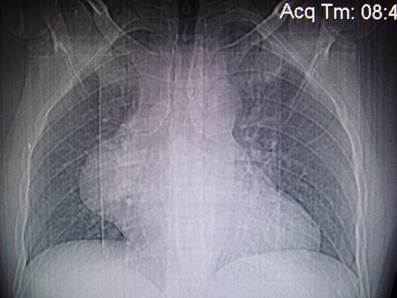

При данной рентгенологической картине патологическое образование локализуется

A) Исходит из аорты, так как расширен ее восходящий отдел

B) В средостении, потому что широким основанием прилежит к нему

C) В легком, потому что наибольшая часть тени расположена в легочном поле

D) Исходит из ребра, так как широким основанием прилежит к ним

E) Исходит из позвоночного столба, так как локализуется в реберно-позвоночном углу.

{Правильный ответ}= С